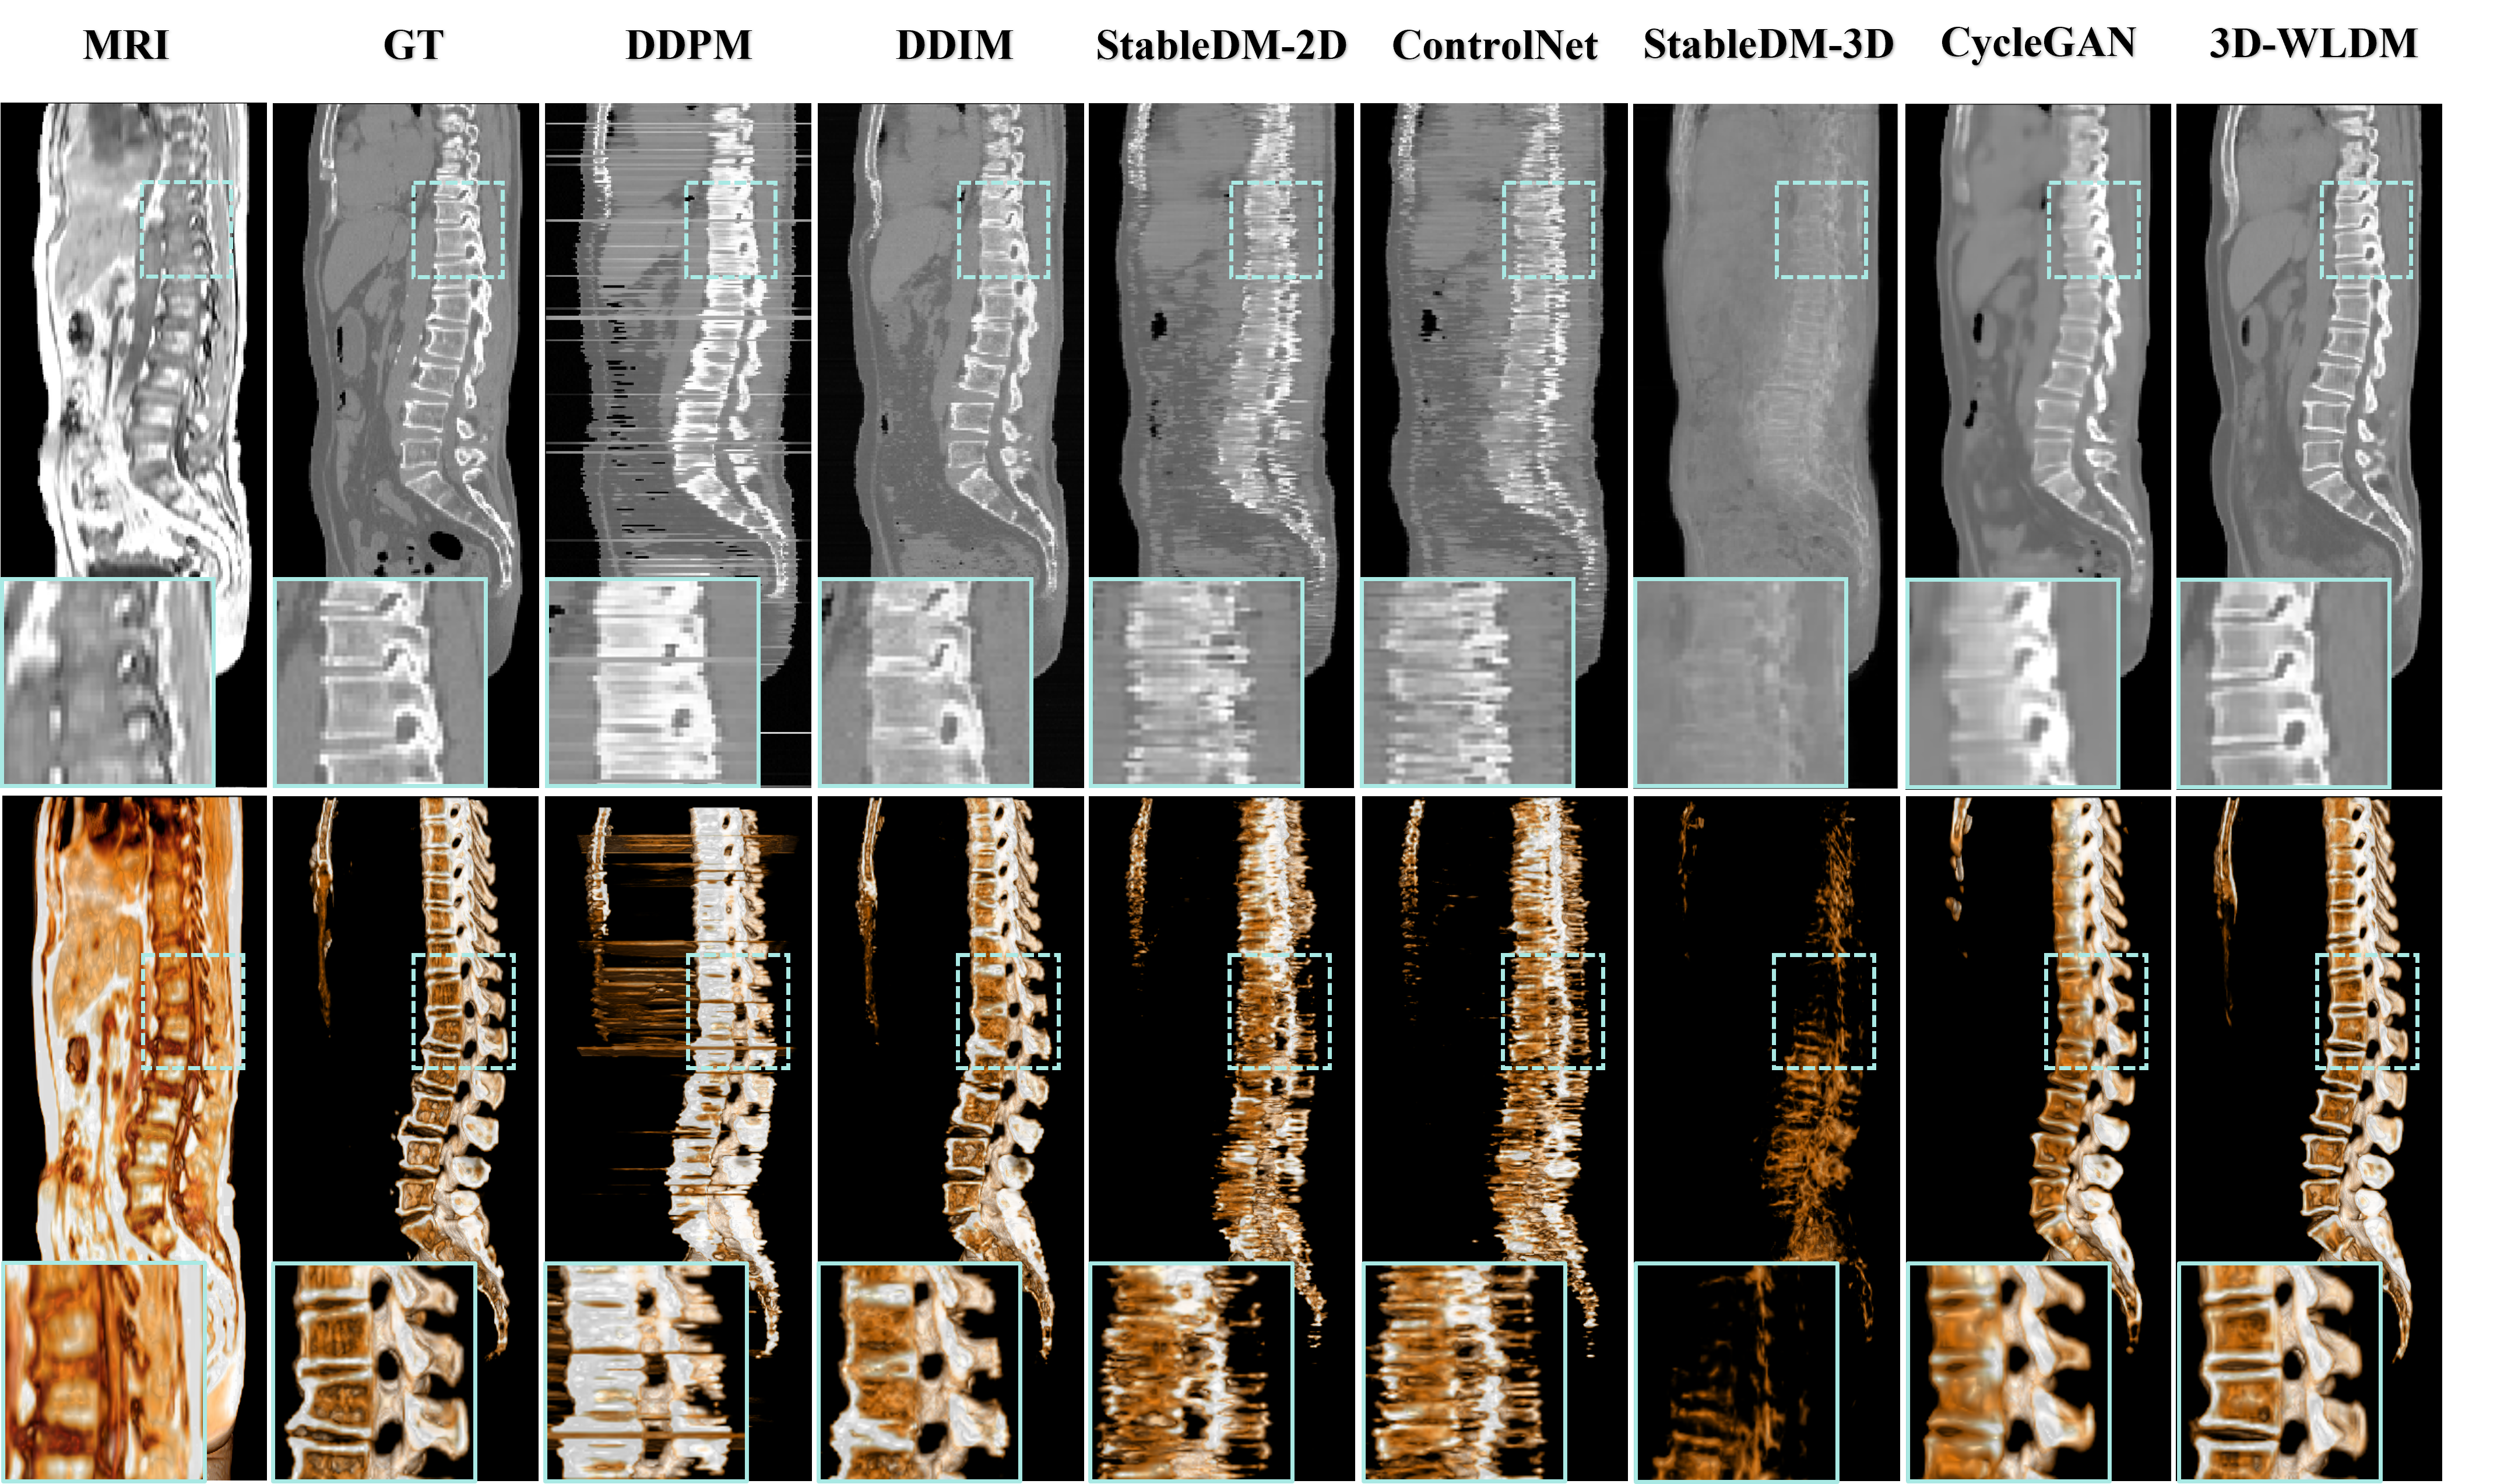

IV-B3 Spine Reconstruction Analysis

The spine presents a significant challenge for MR-to-CT synthesis due to the inherently low soft-tissue contrast and blurred cortical boundaries in MR images. These limitations substantially affect the accuracy of vertebral bone reconstruction—an essential component for downstream clinical applications such as radiotherapy planning and PET/MR attenuation correction. To evaluate the fidelity of synthetic vertebral structures, sagittal-plane slices and rendered 3D spine visualizations are shown in Fig. 6, revealing notable differences among competing methods.

Consistent with observations from the axial-plane results in Fig. 5, both DDPM and DDIM fail to reconstruct anatomically accurate spinal structures. DDPM exhibits poor trabecular bone detail and fails to preserve internal vertebral architecture. Although DDIM shows improved contour alignment, it introduces contrast inversions at intervertebral boundaries, indicating erroneous intensity modeling. These findings suggest that pixel-space diffusion models offer better geometric alignment but are limited in capturing realistic image contrast and bone microstructure. StableDM-2D and ControlNet produce visually appealing outputs in the axial view, with enhanced contrast and texture fidelity. However, they fail to maintain structural continuity in the spine across sagittal slices, resulting in fragmented and anatomically implausible vertebral columns. This misalignment likely stems from inadequate structural encoding during latent-space diffusion, where spatial correlations between MR inputs and CT targets are poorly preserved. CycleGAN yields high-contrast outputs but fails to reconstruct the fine trabecular architecture of the spine. This is attributed to the network’s difficulty in modeling cortical bone features, which appear hyperintense and sharply contoured in CT but indistinct in MR. Consequently, large portions of the spine are absent or inaccurately depicted, particularly in coronal slices (Fig. 5), reducing the method’s utility in bone-critical applications.

In contrast, the proposed 3D-WLDM model achieves markedly improved vertebral bone reconstruction. It preserves global structural alignment with MR inputs while capturing fine-grained details of both cortical and trabecular bone. These results underscore the effectiveness of the model’s wavelet-based multiscale representation and structure-modality disentanglement in overcoming the intrinsic limitations of MR imaging for bone synthesis.